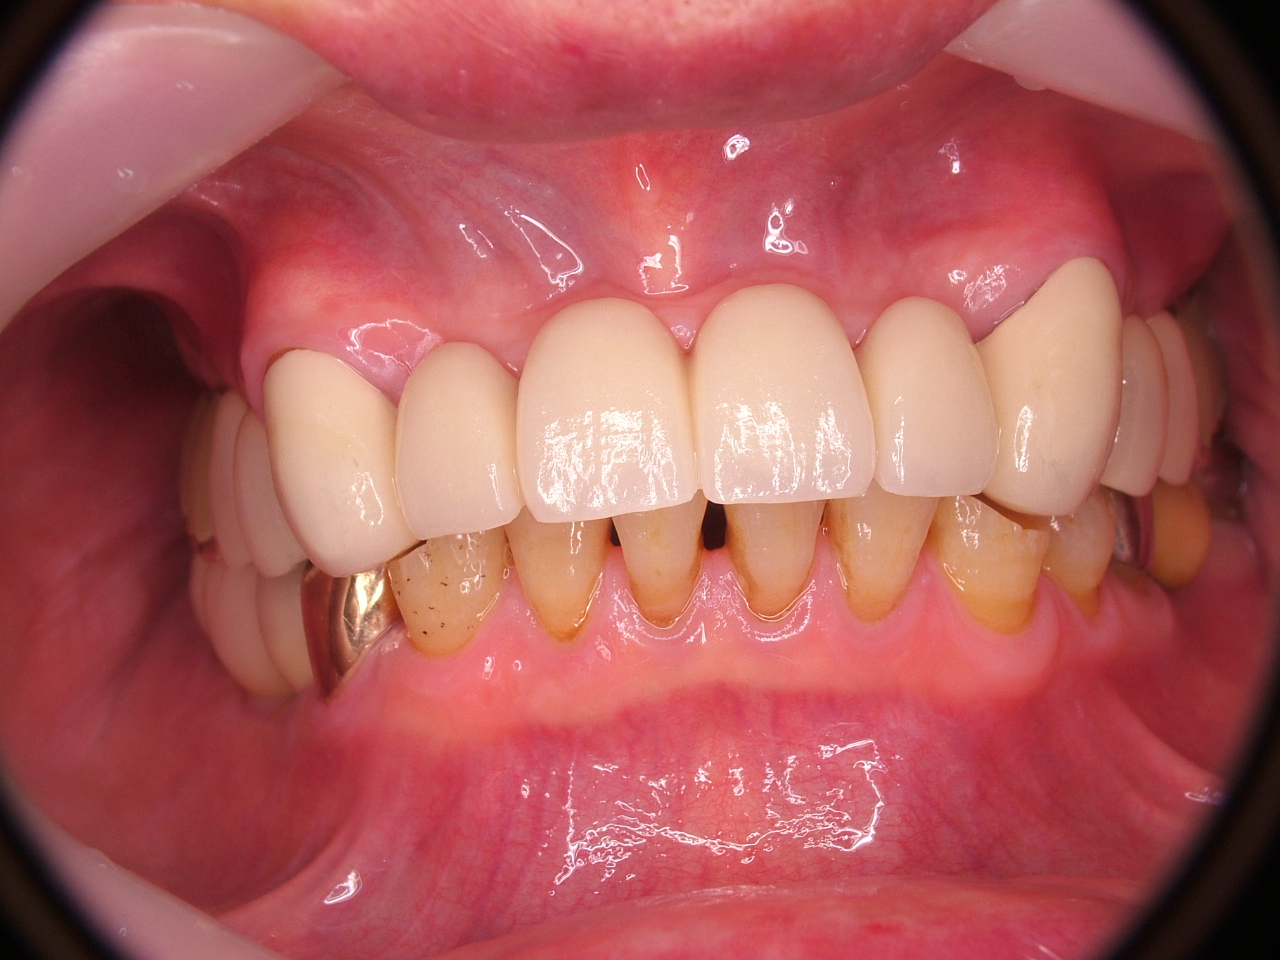

[임플란트] 제목 : 상악 전악 및 하악 구치부

틀니를 벗고 임플란트로